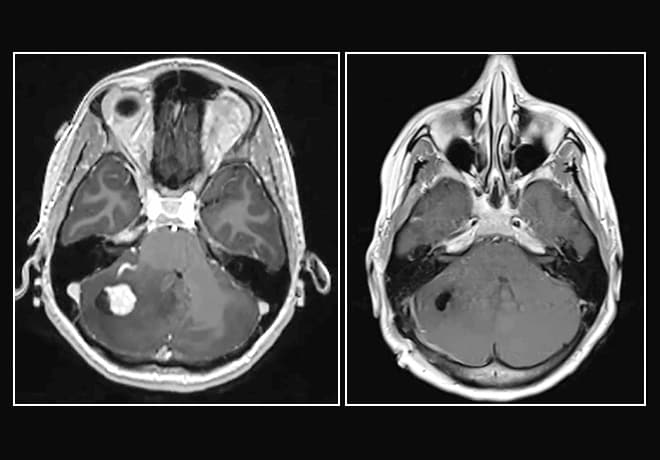

On the left, preoperative MRI of a hemangioblastoma shows significant swelling. On the right, MRI shows complete removal of the lesion after minimally invasive surgery.